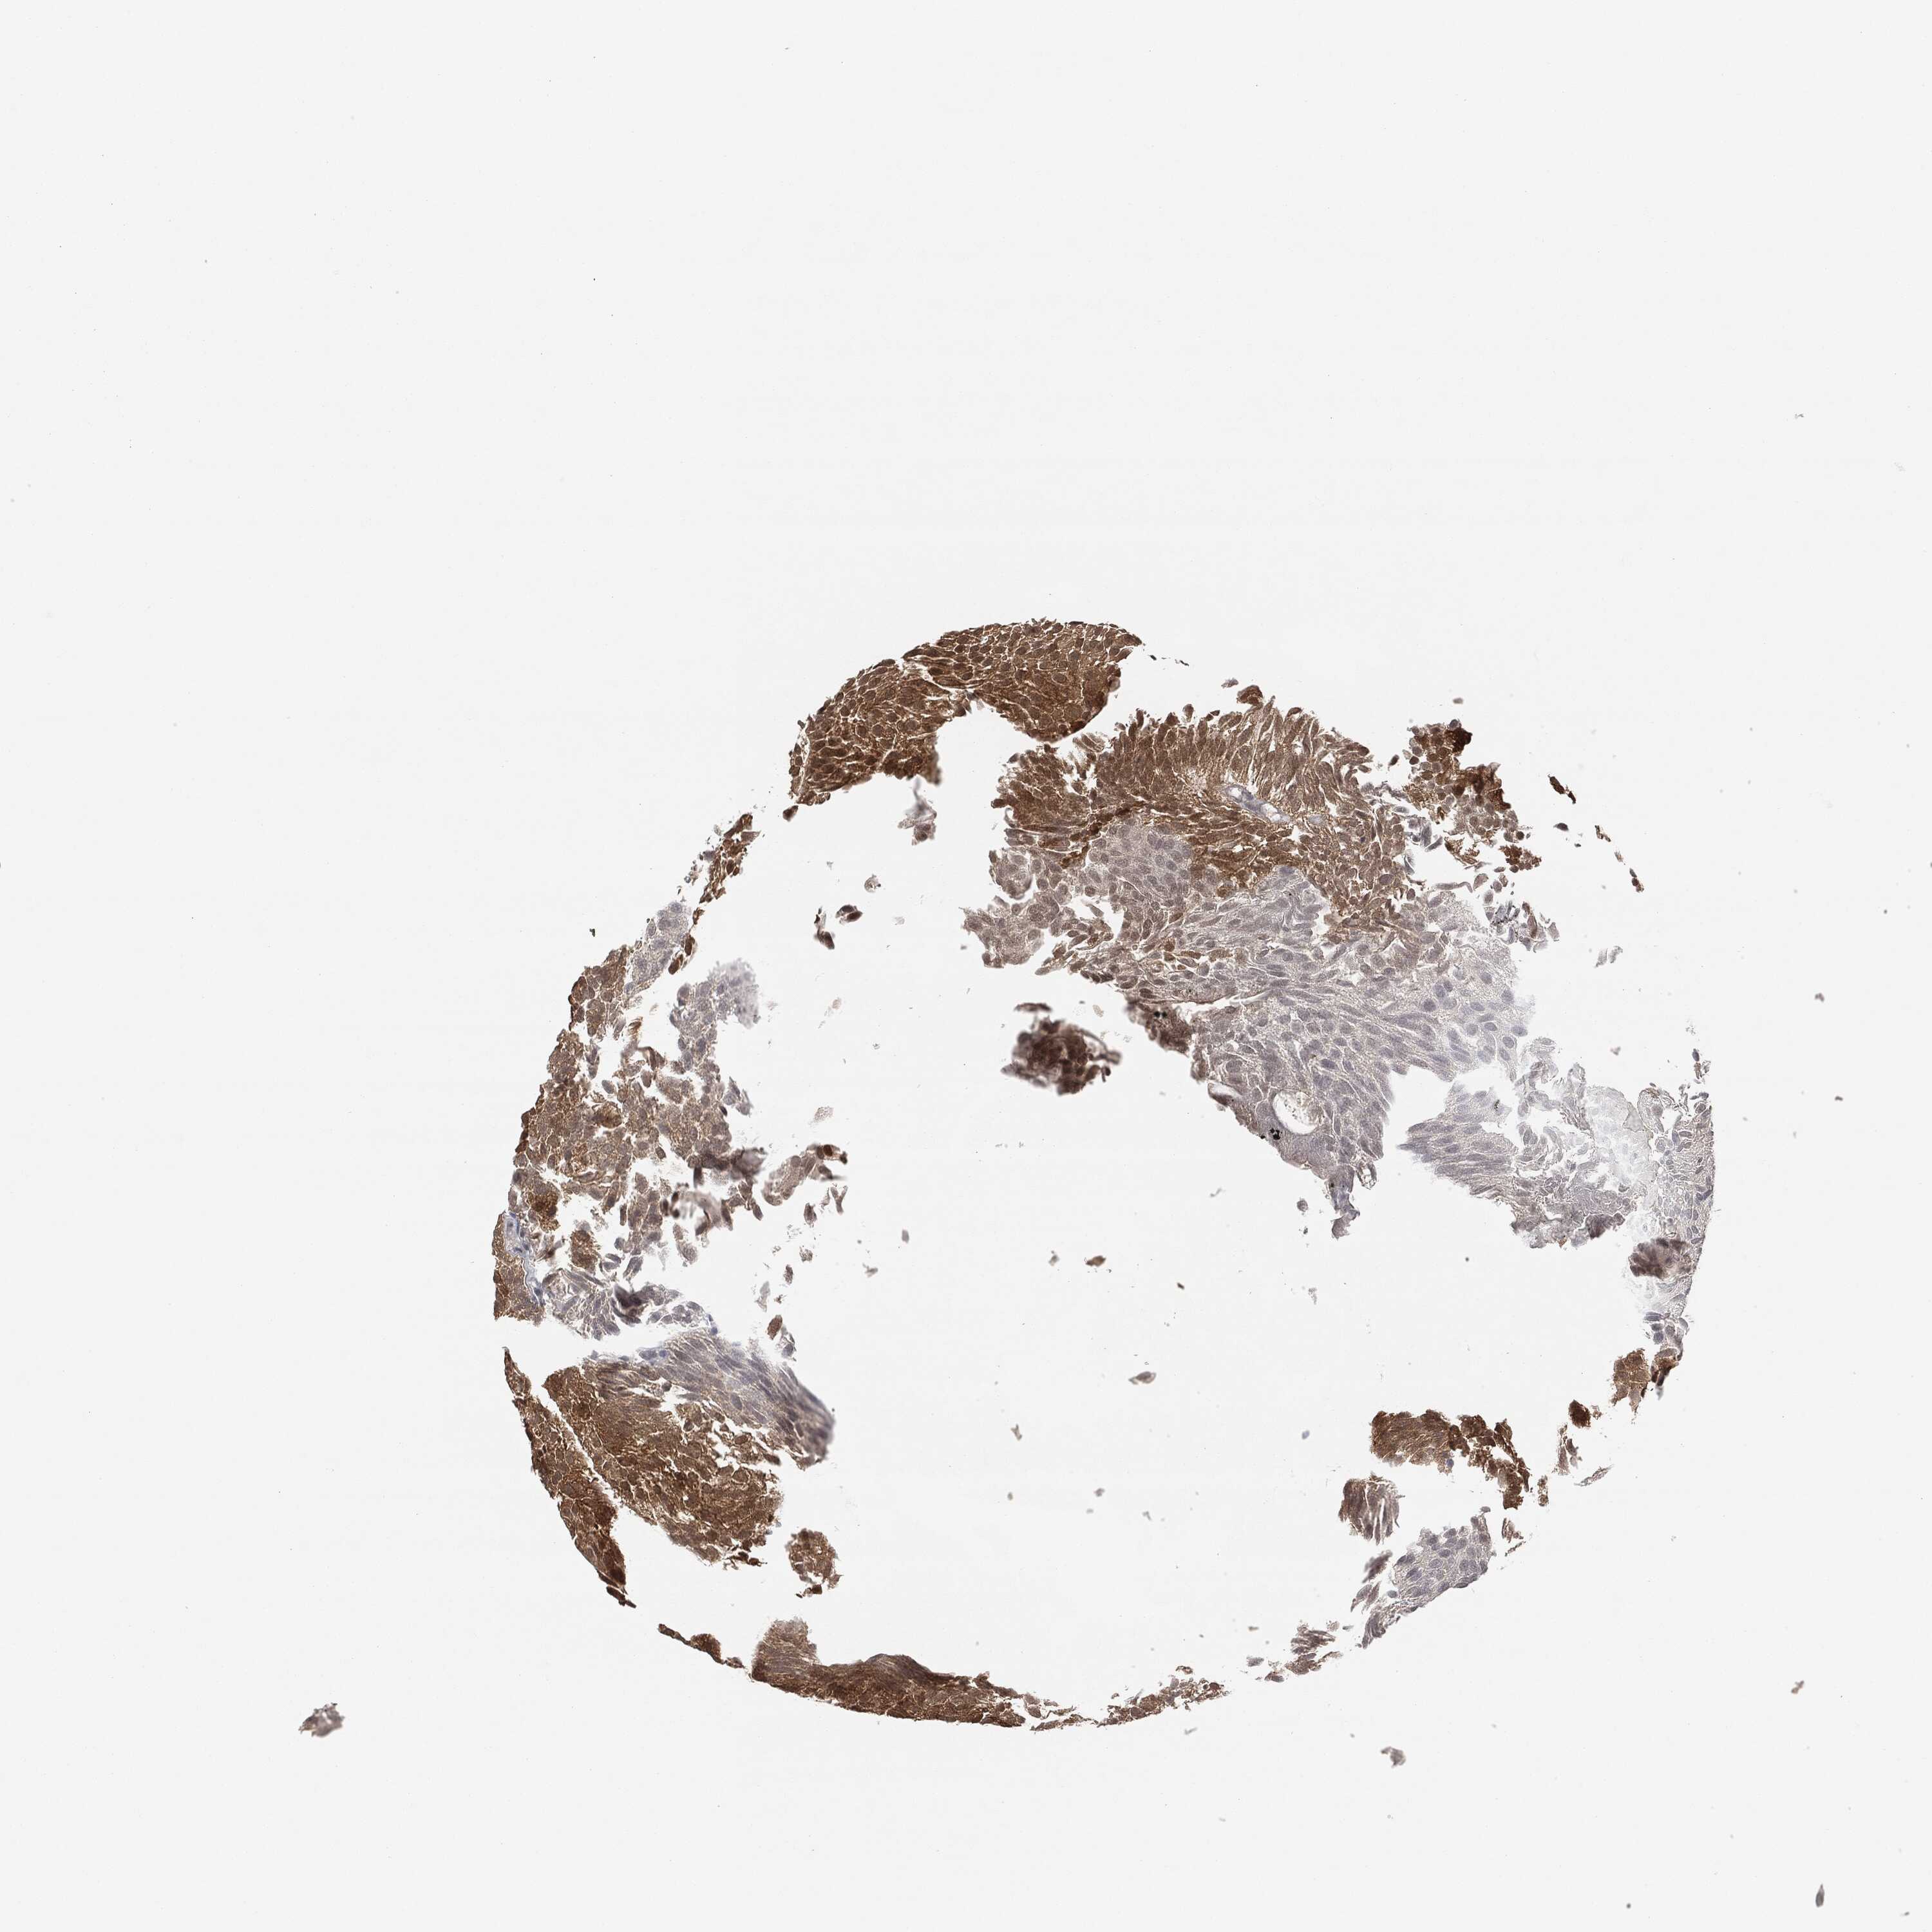

UROTHELIAL CANCER - Protein expressioni

A mouse-over function shows sample information and annotation data. Click on an image to view it in a full screen mode. Samples can be filtered based on level of antibody staining by selecting one or several of the following categories: high, medium, low and not detected. The assay and annotation is described here.

Antibody stainingi

Antibody staining in the annotated cell types in the current human tissue is reported as not detected, low, medium, or high, based on conventional immunohistochemistry profiling in selected tissues. This score is based on the combination of the staining intensity and fraction of stained cells.

Each image is clickable and will lead to virtual microscopy that enables deeper exploration of all samples and also displays staining intensity scores, fraction scores and subcellular localization as well as patient and tissue information for each sample.

Antibody CAB000102

Antibody CAB080442

Urothelial carcinoma, High grade

Urothelial carcinoma, Low grade

Adenocarcinoma, NOS